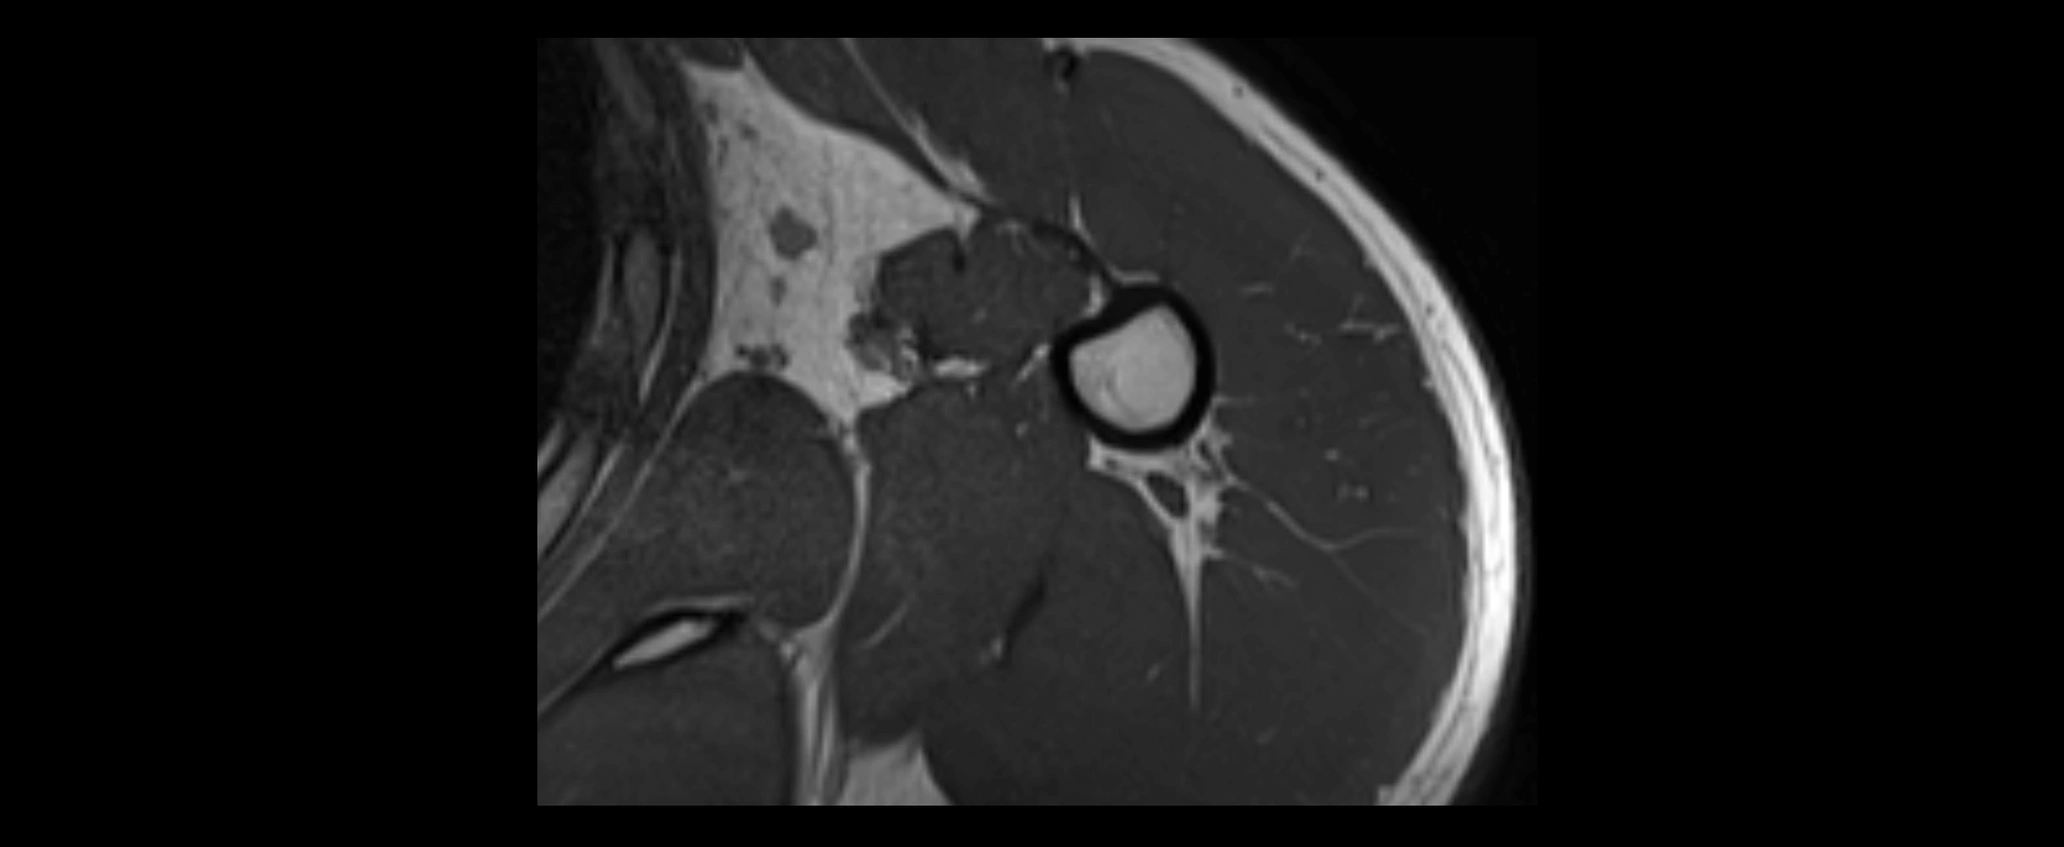

MRI images

image